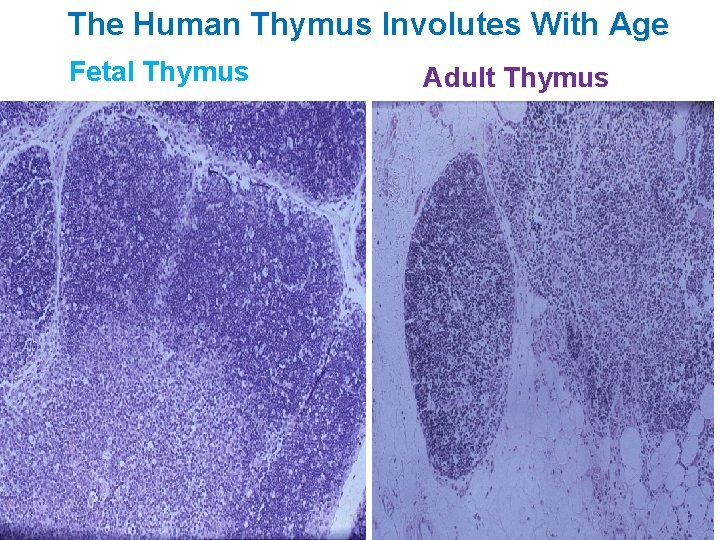

The Human Thymus Involutes With Age Fetal Thymus Adult Thymus